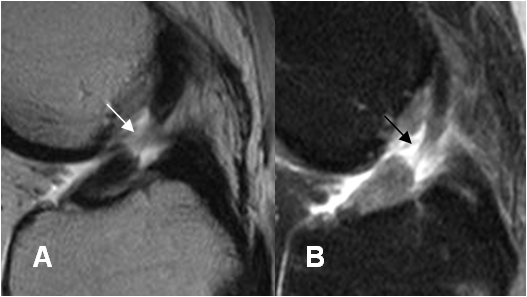

Fig 100. Ruptura LCA.

A: RM sagital en T2 y B: RM sagital en STIR. Ruptura completa de las fibras del LCA, en el tercio medio.